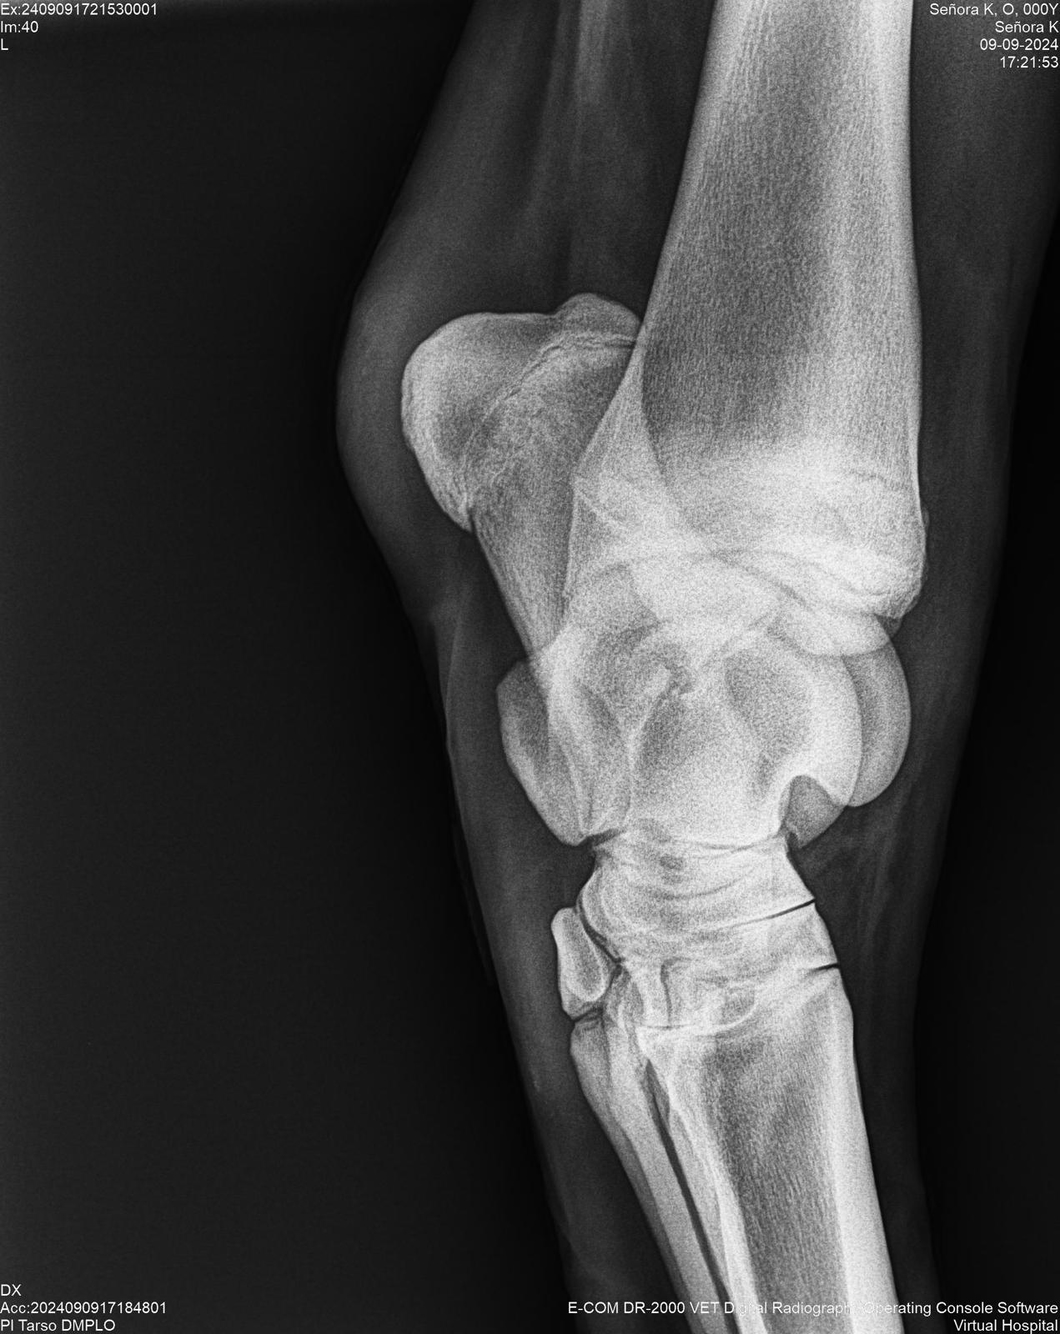

LOTE 44, SEÑORA K

Identificador: #291147-

Generacion 2022